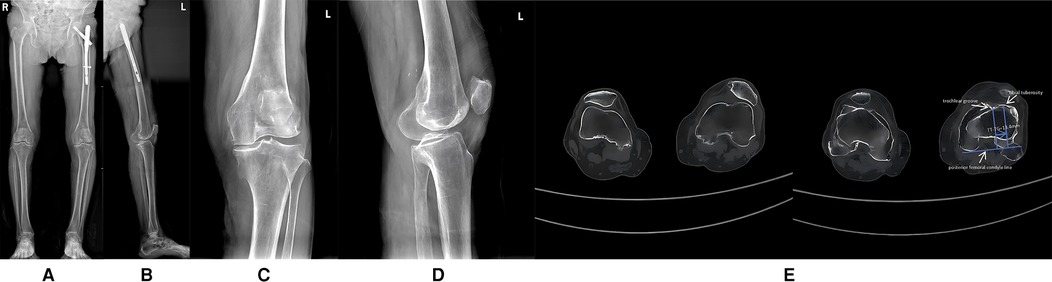

Clinical examination revealed a mild varus deformity of the left lower limb, with approximately 10° of varus alignment. Mild tenderness was noted over the medial patella. The active range of motion of the left knee joint was 0–110°, while passive range reached 0–120°. Patellar dislocation occurred when the knee is flexed at 40° (refer to Supplementary Video S1), with tolerable pain and a visual analogue scale (VAS) score of 5 (6), the knee society score (KSS) clinical score was 57, functional score was 15, and the Oxford Knee Score (OKS) was 41. When the joint is extended, the patella can be reduced; however, forced reduction impedes further knee flexion. The knee remained stable under varus and valgus stress, with negative anterior and posterior drawer tests at 90° of flexion. Full-length frontal radiograph of the lower limb and frontal radiograph of left knee joint demonstrated degenerative changes in both knees, including medial compartment narrowing and multiple osteophyte formation. Possible osteochondromas were noted at the medial upper tibial margins bilaterally, along with bilateral knee varus and patellar dislocation (refer to Figures 1AD). Computed tomography (CT) further validated the aforementioned diagnosis (refer to Figure 1E).

Figure 1

Figure1-Figure4 are preoperative iradiograph: degenerative changes in both knee joint, bilateral genu varum, possible osteochondroma on the medial border of the upper ends of both tibias, suspected patellar dislocation, and the right femur with intramedullary rod fixation. Figure5 revealed left patellar dislocation, is a CT scan series showing axial slices of the knee with anatomical landmarks labeled for alignment assessment.

Figure 1. (A) Full-length frontal radiograph of the lower limb; (B) Full-length lateral radiograph of the lower limb; (C) Frontal radiograph of left knee joint; (D) Lateral radiograph of left knee joint; (E) CT axial images of left knee joint. [The tibial tuberosity–trochlear groove (TT-TG) distance is 13.4 mm].